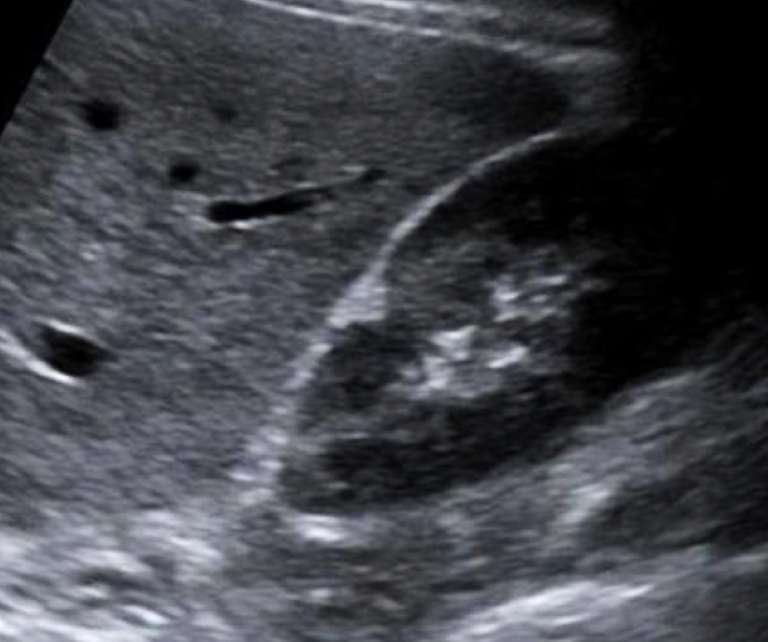

SONO (neonates vs. adults): autosomal recessive polycystic kidney disease (ADPKD)

neonates:

enlarged kidneys

adults:

enlarged kidneys with asymmetrical cysts in cortex and medulla

loss of reniform shape (kidney shape)

?? describe

autosomal dominant polycystic kidney

“multiple cystic structures noted throughout RK. ?polycystic kidney dz”

??

autosomal dominant polycystic kidney (ADPKD)